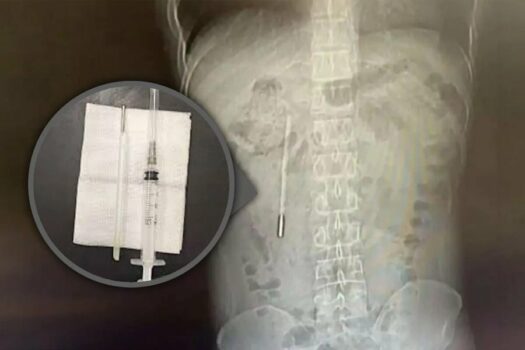

32-vjeccari është paraqitu në stomak me dhimbje në stomak. Pas ekzaminimeve, mjekët zbuluan se një termometër që ai e kishte gëlltitur kur ishte fëmijë ishte ende brenda tij.

Kirurgët e hoqën me sukses termometrin gjatë një operacioni.